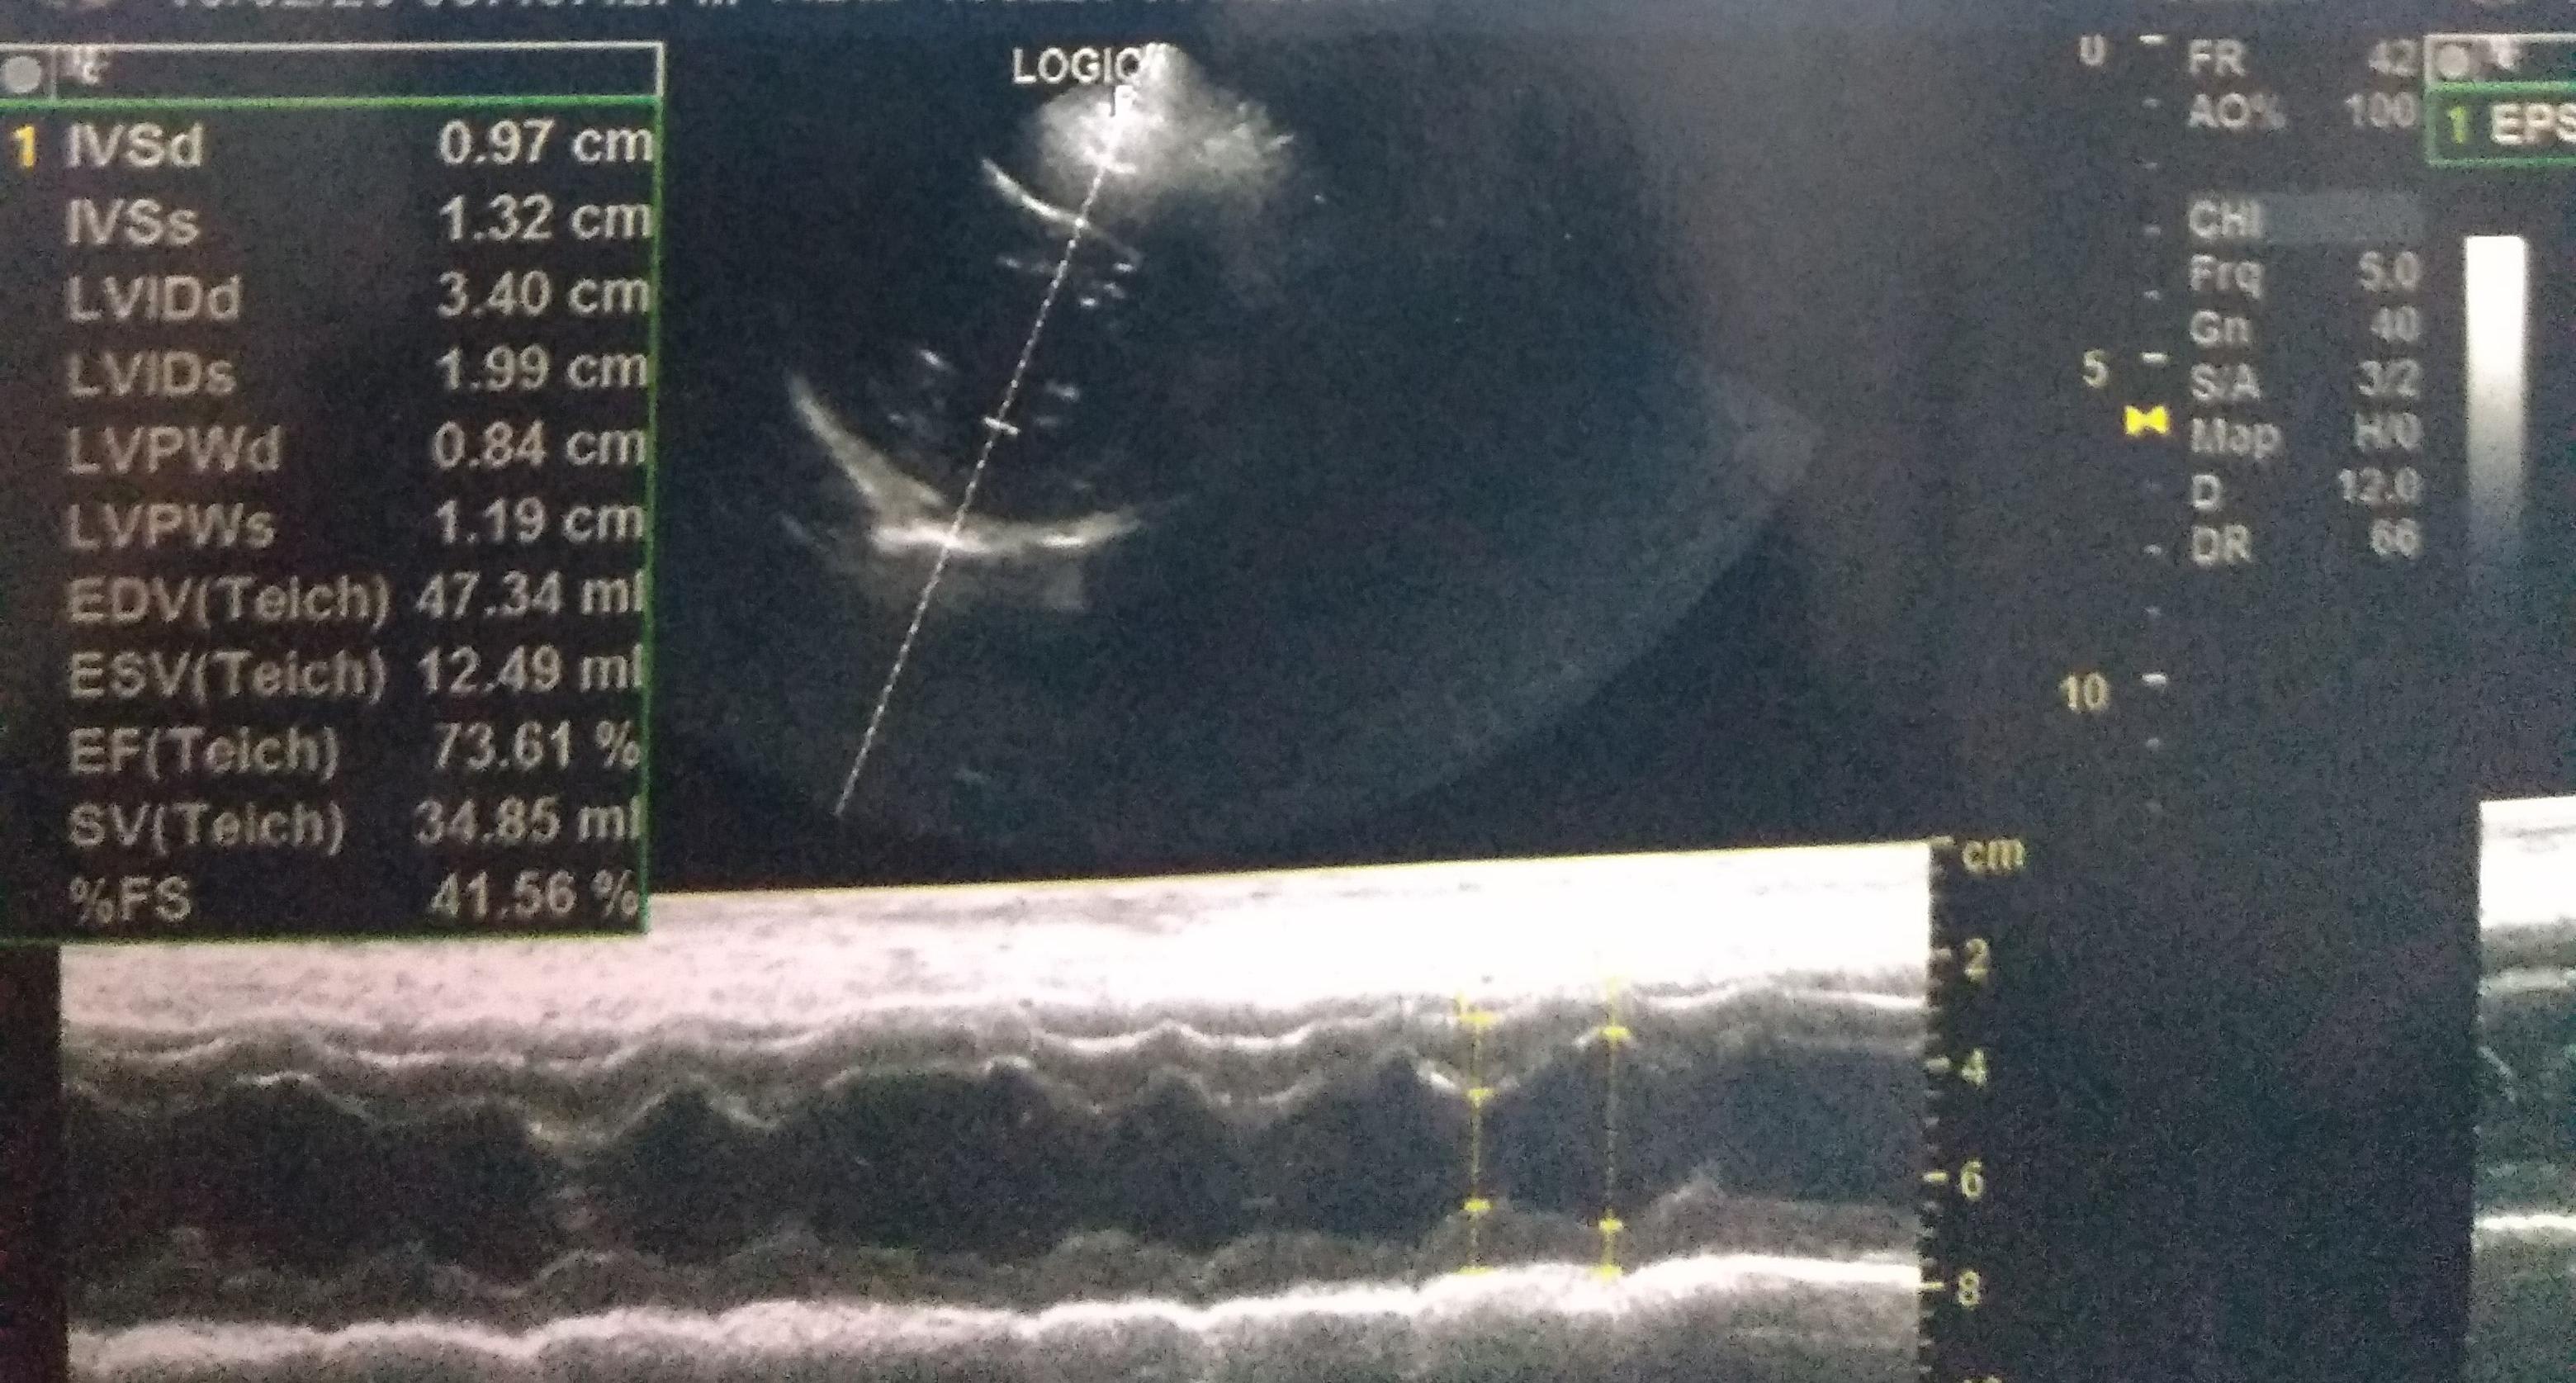

Vet told that my dog's heart is slow.pics of echocardiogram.what these measurements mean n is there any abnormality present?is anything else required?how to improve her heart? do's n don'ts?plz explain these measurements meanings.

Please, you need to speak to the vet that did the imaging so they can explain everything to you. We do not use those same units of measure in the U.S. so I cannot correlate their relevancy. Also the size of the dog needs to be taken into consideration with the measurements and you have not provided that information to us. All I can tell you is that the fractional shortening (FS) is a normal percentage. FS refers to the size of the ventricle and whether it is functioning normally. In general, normal fractional shortening (FS%) is 28%–45% in the dog; your dog's is 41.56% The Ejection fraction (EF) is also normal. EF is a measurement of the percentage of blood leaving your heart each time it contracts. Anything over 55% is normal. Your dog's is 73.61%. I have no idea why they are saying the heart is slow. You need to speak to them directly to get clarification.